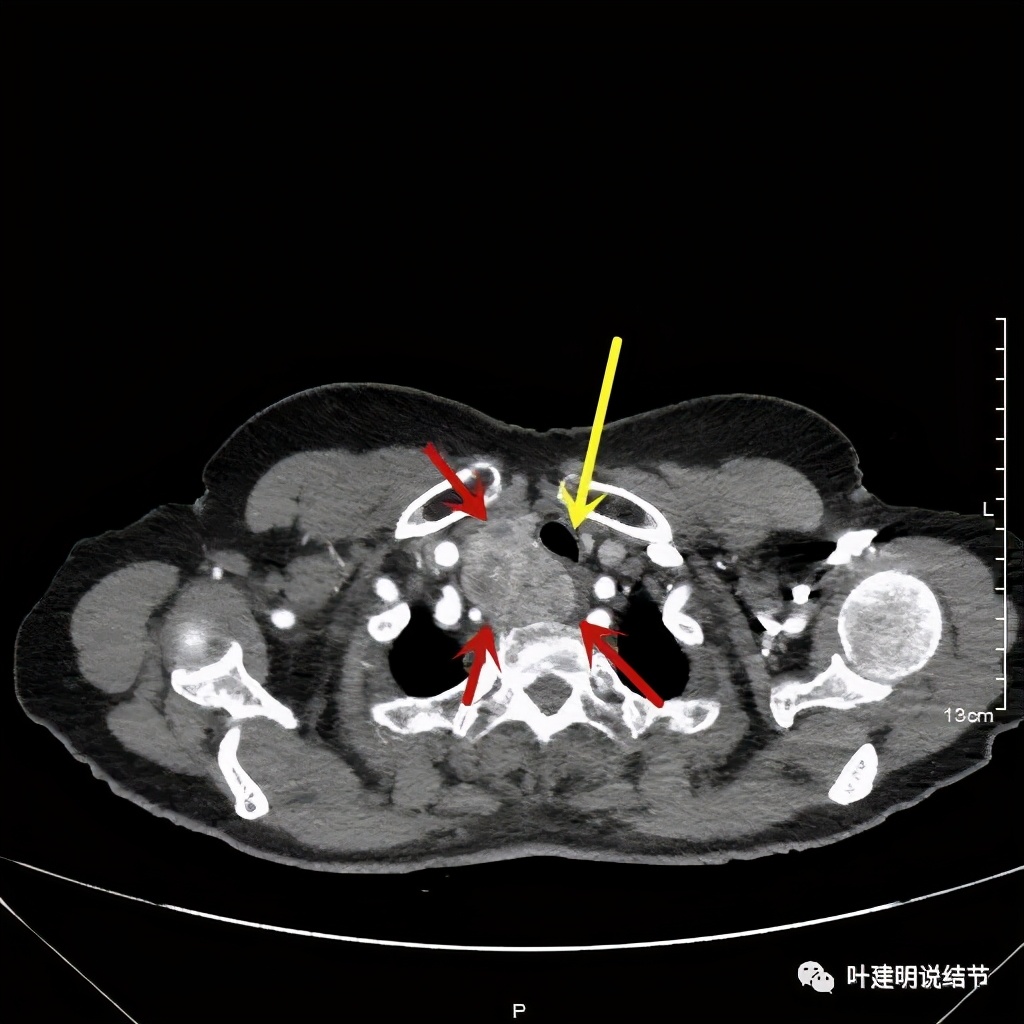

金华地区的某A,今年已经76岁了,近段时间觉得胸闷不适,还有刺激性咳嗽,总是不会好,到当地医院查了胸部CT,发现是纵隔肿瘤。当地医生建议她到金华市中心医院做下气管镜下穿刺活检,以明确肿瘤性质。因为认识我们医院的某外科主任,所以又建议她来找我,结果我一看她从当地带来的片子,是纵隔内巨大的占位,与气管关系密切,位于气管右侧、食管右前侧、上腔静脉左侧、无名静脉后侧,被诸多结构包绕着,而且肿瘤密度不均,靠气管与无名静脉侧间隙不清,首先考虑纵隔内恶性或交界性肿瘤,由于年纪这么大,手术风险较高,若与气管有侵犯,则手术达不到根治,我也觉得应该先行经气管镜下的穿刺活检,明确病理后再考虑怎么办。所以让某A住到呼吸内科去,打算行气管镜下纵隔肿瘤穿刺活检。因当地的片子扫到胸顶部为止,没有做增强,我们先取本院增强片子上达胸顶,下达肿瘤下缘的范围来看看肿瘤的样子:

胸顶就开始有肿瘤了,黄色示受压迫移位的气管,红色示肿瘤